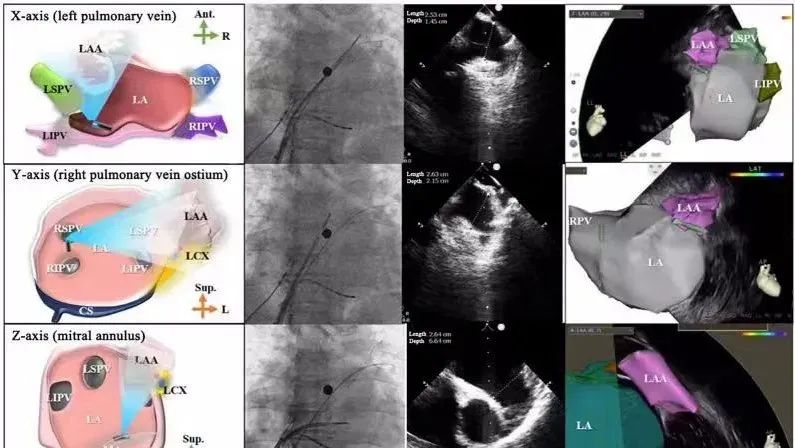

一種與心導(dǎo)管檢查相結(jié)合的超聲心動(dòng)圖診斷新興技術(shù),通過將超聲探頭置于心腔內(nèi)部,發(fā)射并接收超聲信號,來精確獲取心臟解剖結(jié)構(gòu)、心臟血流動(dòng)力學(xué)等信息的實(shí)時(shí)成像。與其他影像技術(shù)相比,ICE技術(shù)具有操作簡單、無輻射、安全性高、手術(shù)效率高、實(shí)用等優(yōu)勢,ICE在很大程度上有望取代經(jīng)食道超聲心動(dòng)圖(TEE),成為電生理和結(jié)構(gòu)性心臟病領(lǐng)域的理想成像方式。

心腔內(nèi)超聲(ICE)技術(shù)壁壘極高,國內(nèi)主要廠商核心部件仍舊為進(jìn)口,集成了超聲和圖像處理最前端技術(shù),包括超聲探頭、線纜、軟件成像算法等,是當(dāng)前內(nèi)窺超聲方向最具挑戰(zhàn)的領(lǐng)域。ICE的應(yīng)用經(jīng)歷了2D平面成像、3D三維立體成像、以及4D的實(shí)時(shí)三維立體成像階段。